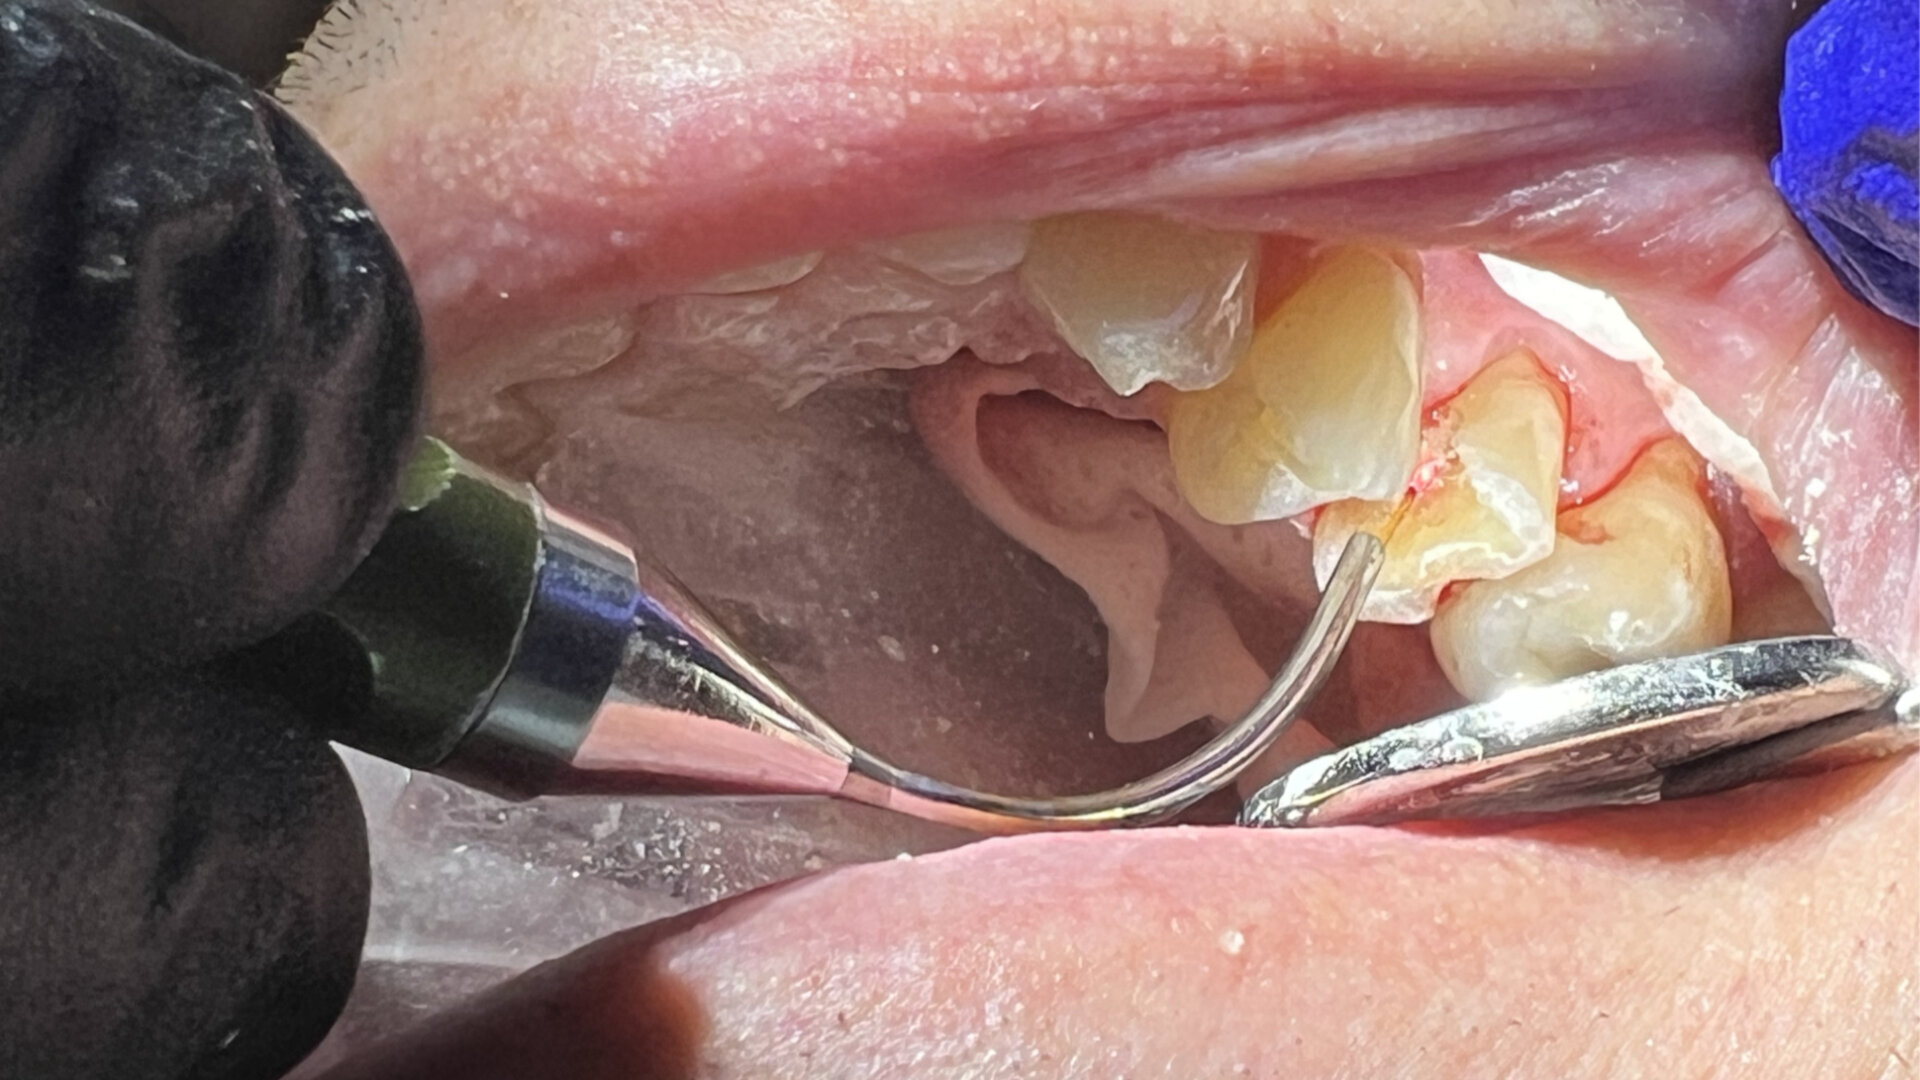

Local anaesthetic was infiltrated into the buccal vestibule. The caries and affected tooth structure were removed with carbide and diamond burs. A pulpal exposure was not observed, but thin tooth structure was noted covering the pulp (Fig. 11). The Nd:YAG laser was set on the ablation setting and applied to the area over the thin dentine overlying the pulp at 50–75 J. The laser was then used on the same setting up to 162 J to sterilise the surrounding tooth structure and for biostimulation as described in the prior case. A small amount of GC FujiCEM was placed to cover the underlying pulp. A core build-up was then applied utilising RelyX Unicem resin on the surrounding sound tooth structure to ensure a good bond between the core material and dentine. Crown preparation of the tooth was completed. An impression was taken, and a provisional crown was fabricated and cemented with IRM. The patient returned for definitive crown insertion two weeks later and reported a lack of sensitivity during the period since her prior appointment. The provisional crown was removed, the definitive crown was luted with RelyX Unicem, and the occlusion checked and adjusted as needed.

Fig. 11: Pulpal tissue seen below a thin layer of dentine after caries removal.

Local anaesthetic was infiltrated into the buccal vestibule. The caries and affected tooth structure were removed with carbide and diamond burs. A very small pulpal exposure was noted (Fig. 14), and after discussion with the patient of the options of immediate endodontic treatment or laser treatment of the exposure and a core build-up followed by crown placement if no symptoms arose over the next few weeks, the patient opted for the laser pulp treatment option. The Nd:YAG laser was set on the ablation setting and applied to the area of the pulpal exposure at 50–75 J (Fig. 15). The laser was then used on the same setting up to 162 J to sterilise the surrounding tooth structure and for biostimulation as described. A stabilising pin was placed into the dentine on the lingual aspect to aid in stabilisation of the core build-up. A small amount of GC FujiCEM was placed to cover the underlying pulp. A core build-up was then applied utilising RelyX Unicem resin on the surrounding sound tooth structure to ensure a good bond between the core material and dentine (Fig. 16). Crown preparation of the tooth was then completed. An impression was taken, and a provisional crown was fabricated and cemented with IRM. The patient returned for a postoperative check of the tooth after one week and reported a lack of any sensitivity to temperature or occluding on the provisional crown. The impression was sent to the laboratory for crown fabrication. The patient then returned for definitive crown insertion two weeks later and continued to report a lack of sensitivity. The provisional crown was removed, the definitive crown was luted with RelyX Unicem, and the occlusion checked and adjusted as needed.